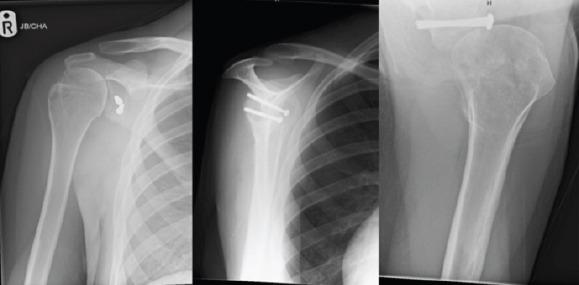

A 16-year-old boy presented to the emergency department with reduced range of movements in both shoulders. Six weeks prior he had suffered an epileptic seizure. X-rays confirmed bilateral anterior shoulder dislocations with displaced greater tuberosity (GT) fractures. Staged open reduction was performed in the right and then left shoulder. Coracoid osteotomy with takedown of the malunited GT fracture was needed to assist with gradual soft tissue contracture release and a successful relocation. Latarjet procedure was then performed and the GTs were fixed using rotator cuff anchors. At 6 months post-operation, on the right side, he achieved forward flexion to 150o and abduction to 120o. On the left side, forward flexion was 110o and abduction was 90o. X rays showed satisfactory maintenance of the reduction without signs of avascular necrosis of the humeral head.

一名16岁男孩因双肩活动范围受限就诊于急诊科。六周前他曾癫痫发作。X线证实双侧肩关节前脱位伴大结节(GT)骨折移位。先对右侧肩关节进行分期切开复位,随后是左侧。需要进行喙突截骨并切除愈合不良的大结节骨折以辅助逐渐松解软组织挛缩并成功复位。然后进行Latarjet手术,使用肩袖锚钉固定大结节。术后6个月,右侧肩关节前屈达150°,外展达120°。左侧肩关节前屈为110°,外展为90°。X线显示复位维持良好,无肱骨头缺血性坏死迹象。